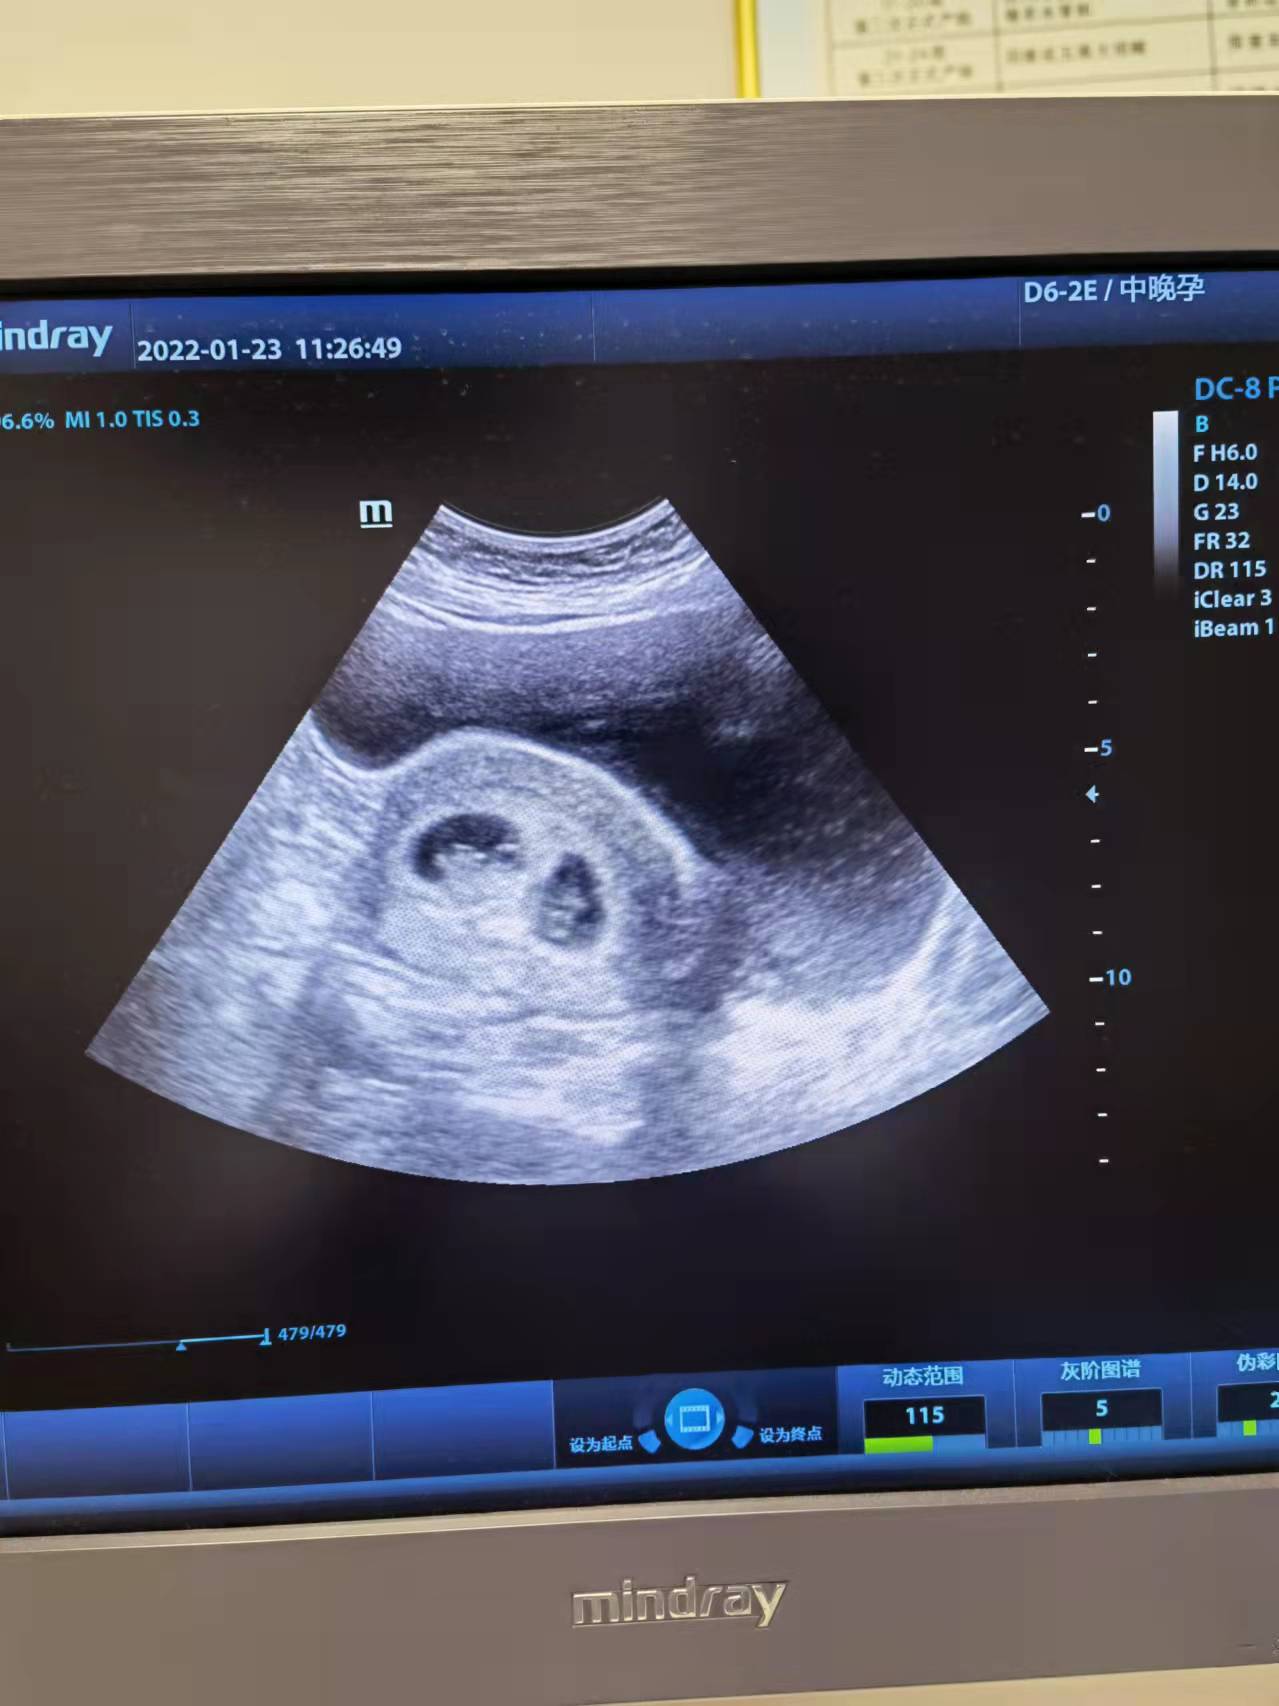

这是1月23日,

杨倩(化名)女士看到

怀孕双胞胎的结果后,

表达出来的幸福和感激的话语。

没想到治疗了一个月,

这次检查怀孕”双胞胎”!